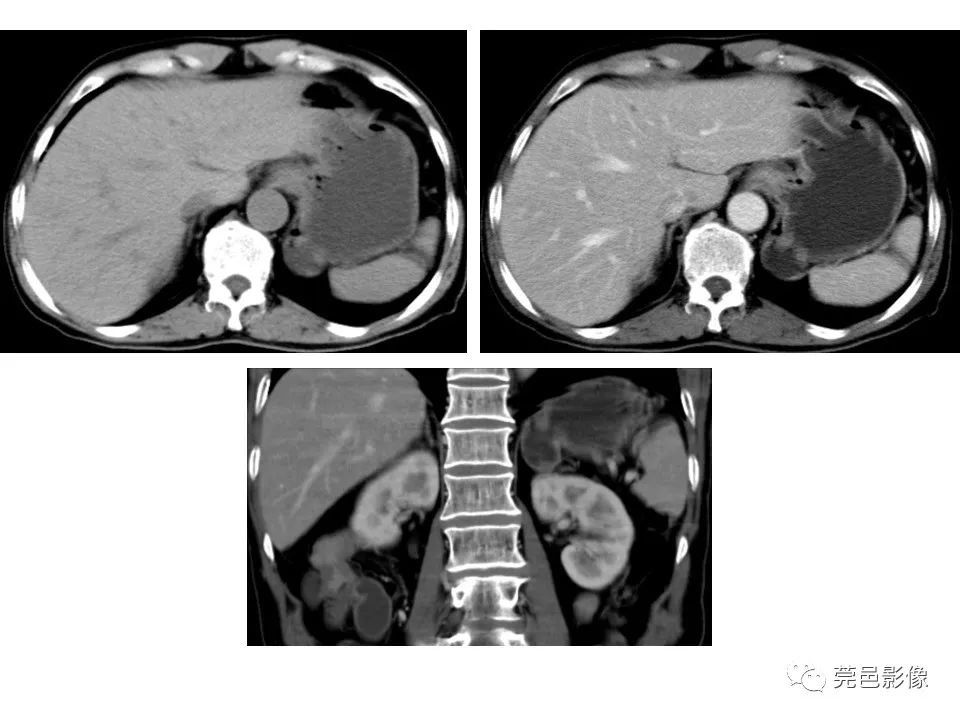

畸形|胃重复畸形CT诊断与鉴别诊断

又称迷走胰腺或副胰。拥有独立的血液供应和神经支配;一种先天性畸形,机制尚不十分清楚。可能是胚胎时期胰腺始基与原肠粘连或穿透原肠壁,并随原肠纵向生长及旋转而被异常移植。或者由异常部位的内胚层细胞异向分化和化生而来;异位胰腺最常发生部位是十二指肠,其次是胃和空肠;症状的产生主要与异位胰腺的解剖位置和并发症有关,与病灶的功能状况和病变发展程度也有一定的关系;正常部位胰腺的任何疾病均可发生于异位胰腺,如胰腺炎、囊肿、腺瘤或腺癌等;消化道内镜为诊断的首选方法。

【 畸形|胃重复畸形CT诊断与鉴别诊断】